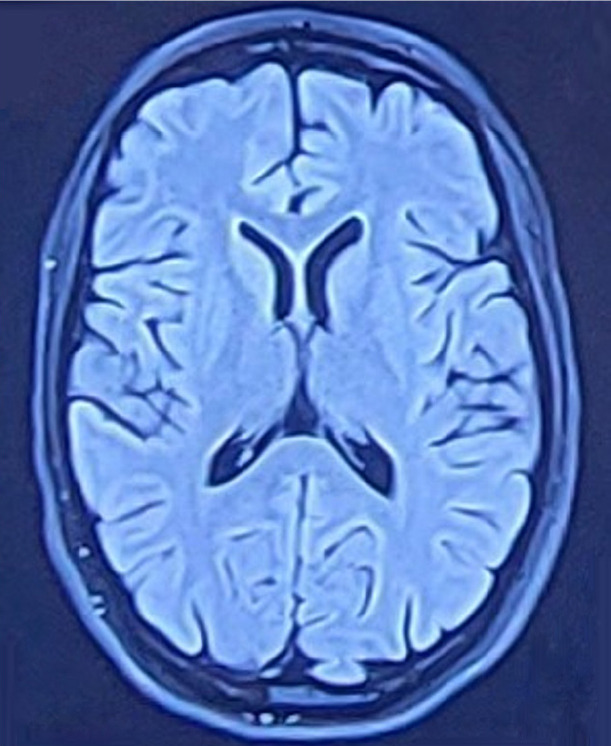

Anti-N-methyl-ᴅ-aspartate receptor (NMDAR) encephalitis is a rare disease with a range of neurological and psychiatric presentations. Antibodies against NMDAR receptor are purported to be pathologic, and the two known potential immunological triggers are tumors and viral infection. In half of the cases, the trigger is not known. We present two cases where stress seemed to have triggered encephalitis. These cases illustrate the possible role of stress in leading to immune dysregulation, which can lead to encephalitis. We review the role of stress in anti-NMDAR encephalitis and possible mechanisms by which stress can trigger an immune dysregulation.